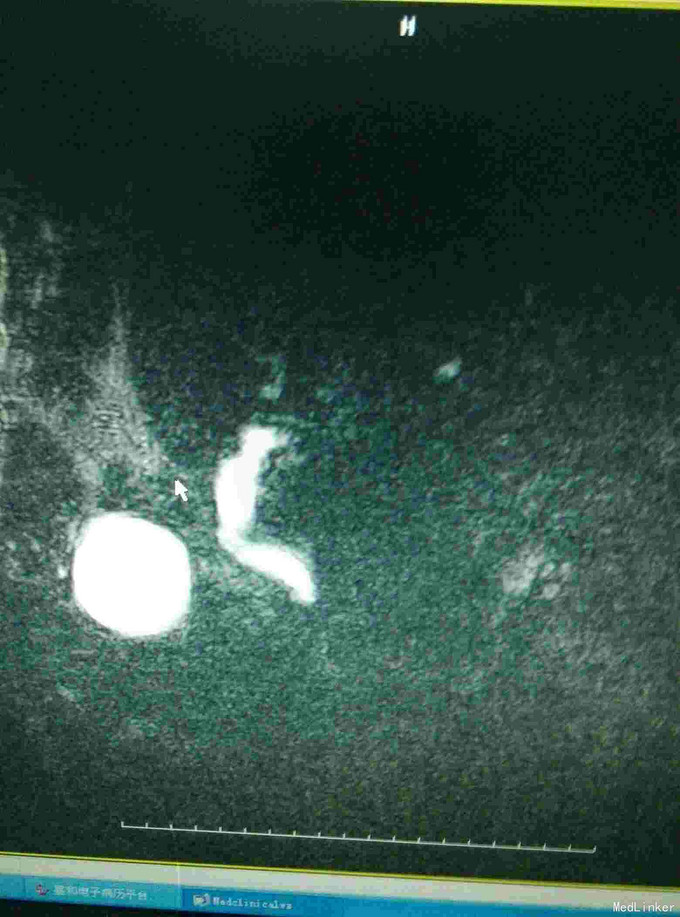

男患,74岁“发现全身皮肤及黏膜黄染2周”,2周前发现皮肤黄染,伴有纳差、厌油,无明显皮肤瘙痒,无发热、寒战,无恶心、呕吐,大便稍稀,无明显白陶土样大便,小便颜色基本正常。

全身皮肤黄染,虹膜黄染,心肺未见异常,腹部稍膨隆,肝区轻度扣击痛,Murphy症阴性。腹部查体腹部B超提示:肝内外胆管扩张,胆囊结石,胆总管下端可见低回声团。MRI如下:

梗阻性黄疸,择日进行了“胆囊切除,胆肠吻合术”,术中见胆囊及上段胆总管明显扩张,下段胆总管塌陷。